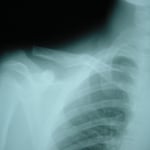

●右鎖骨骨折

当患者さんは手術療法に強く抵抗があり当院での保存療法を選択されました。

骨折部位の短縮転移があたので整復操作が必須になります。運よく短縮転移が矯正されたので保存療法で経過をみました。暑い時期だったので来院の度に固定を外し体を清拭して施術後、新しい下着の上から再度固定をする運びになりました。

骨折部位には超音波、患部以外の所は関節運動、経過を見て軽いマッサージを開始。固定も少しずつ簡易な物へ変更し二カ月後には三角巾のみ、三ヵ月経過すると肩関節の挙上もできるようになりました。

経過良好で完治しました。

左のレントゲンは短縮転位 (受傷時) 右は整復操作をして骨片が重なり合っている状態

整復後包帯と装具で固定。当初は週に2、3回来院してもらいその都度固定は取り外し、体を洗いました。

通常整形外科では取り外しも清拭もしないので暑い時期は患者様には試練です。ストレスは悪影響をもたらします。

局所には超音波治療を施し浮腫みのある指、肘はマサージににより軽減に努めました。6週ほど固定しましたが、各週ごとに固定を楽にしていくのでかなりストレスを軽減できたと思います。3か月目には肩を挙上できるまでになり、筋力強化運動により完治しました。